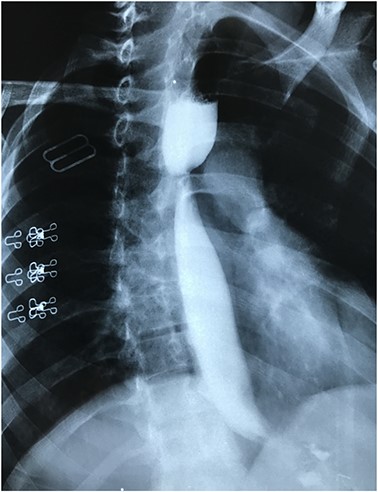

Endoscopic esophageal stent placed for 2 months, with improvement of the clinical condition; after stent removal, she presented with dysphagia, barium study showed esophageal stricture at the middle third of the esophagus at the site of the upper margin of the stent (Fig. 1).

Barium study showing stricture at the middle third of the esophagus with proximal dilatation.